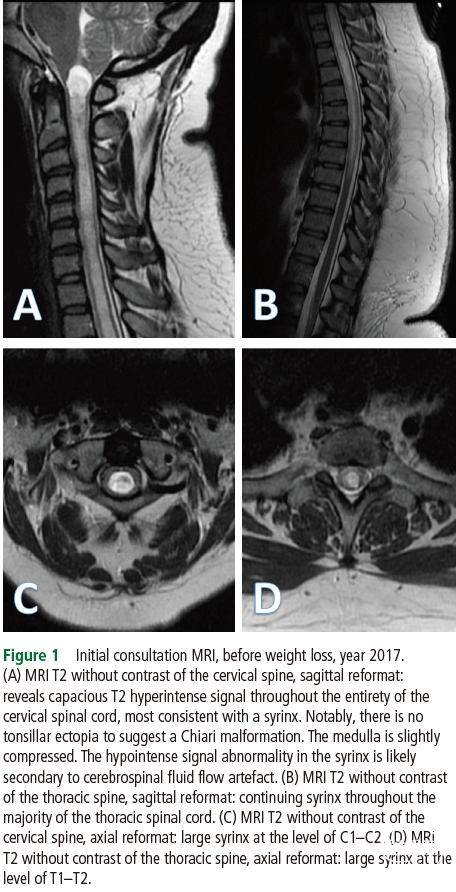

完善全脊柱MRI平扫后,我们注意到巨大的颈椎和胸椎空洞,最大直径为14 mm(图1)。值得注意的是,她没有小脑扁桃体下疝。头颅、全脊柱的增强MRI以及脑脊液(CSF)流动成像序列显示,无隐匿性肿瘤、蛛网膜网和颅内病变。

一年后,患者的神经症状得到缓解,并且令人惊讶的是颈胸段MRI平扫显示空洞几乎完全消退(图2)。尽管症状有所改善,但注意到轻度小脑扁桃体下移(5.2毫米)。鉴于她的影像学和症状改善,我们不再建议对该患者进行神经外科治疗。